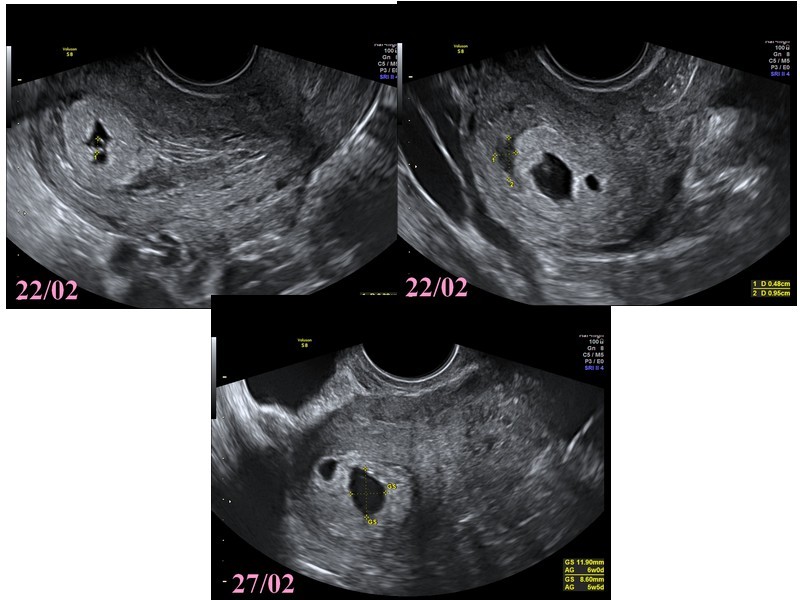

Tenez c'est plus parlant comme ca, ya lecho du 22, ou on voit bien la poche rempli, et les deux poches.

Elle a mesurer la plus grosse poche a 5,34 mm avec un embryon avec une longueur cranio caudale a 2,82 mm.

Vesicule vitelline visualisé

Conclusion de la gygy : grossesse intra uterine evolutive, age gesta 5sa + 3j avec decollement tromphoblastique et presence d'un 2 sac gestationelle plus petit (en train d'involuer?)

Ensuite lecho du 27 (lecho du 22 jai environ 30 images, pour le 27 jen ai 6....)

On voit aussi les 2 poches, qui ont toujours la meme proportionalité de taille.

La plus grosse a etait mesuré a 10,82 mm

Sur ses conclusion la vesicule vitelline n'apparait pas

Pour elle la deuxieme est un decollement... : il ya ecrit "decollement fundique"

Conclusion de la gygy : grossesse intra uterine, age gesta 5 sa + 6j, et dont l'évolutivité reste incertaine.

Ca me parait completement abberant d'avoir 2 avis si differents.